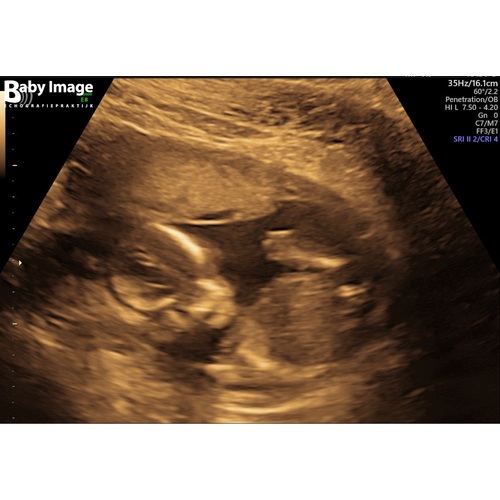

Dit is mijn echo foto van vandaag, mijn vriendinnen heb ik een envelop gegeven met het geslacht en ik weet het zelf ook niet. Vraag me ook af of mensen het geslacht kunnen zien na aanleiding van deze echo.